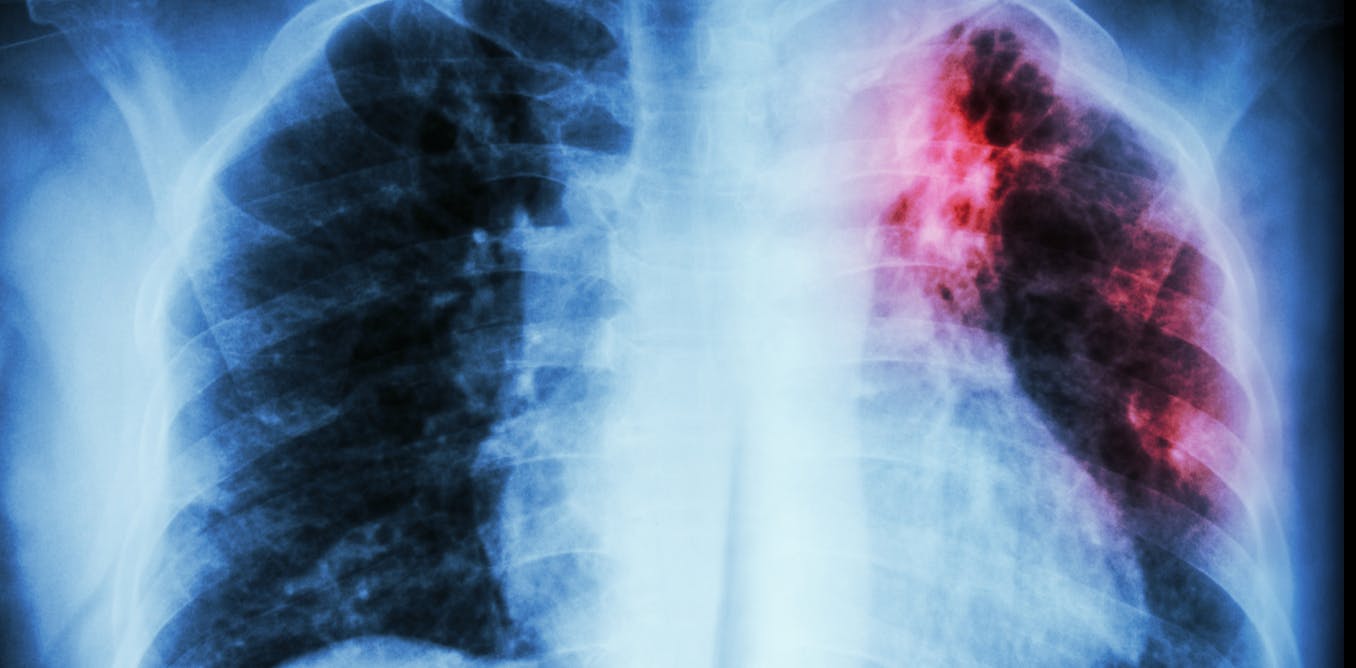

My team and I wanted to identify what variables can predict how a patient responds to TB treatment. So we analyzed more than 200 types of clinical test results, medical imaging and drug prescriptions from over 5,000 TB patients in 10 countries. We examined demographic information such as age and gender, prior treatment history and whether patients had other conditions. Finally, we also analyzed data on various TB strains, such as what drugs the pathogen is resistant to and what genetic mutations the pathogen had.

Looking at enormous datasets like these can be overwhelming. Even most existing AI tools have had difficulty analyzing large datasets. Prior studies using AI have focused on a single data type – such as imaging or age alone – and had limited success predicting TB treatment outcomes.